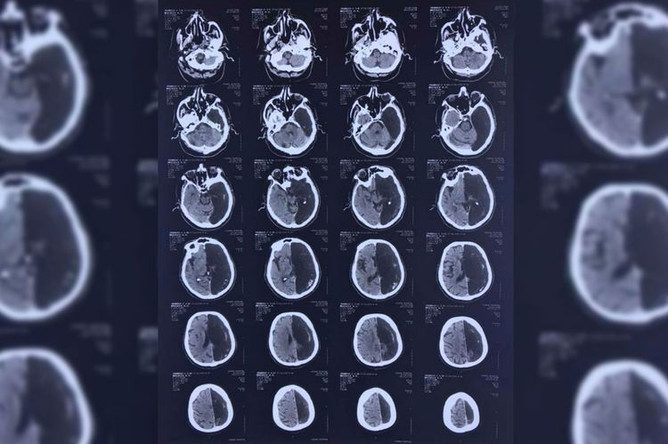

«Ничего не беспокоит»: как живут без половины мозга

В Подмосковье обнаружили уникального пациента с половиной мозга